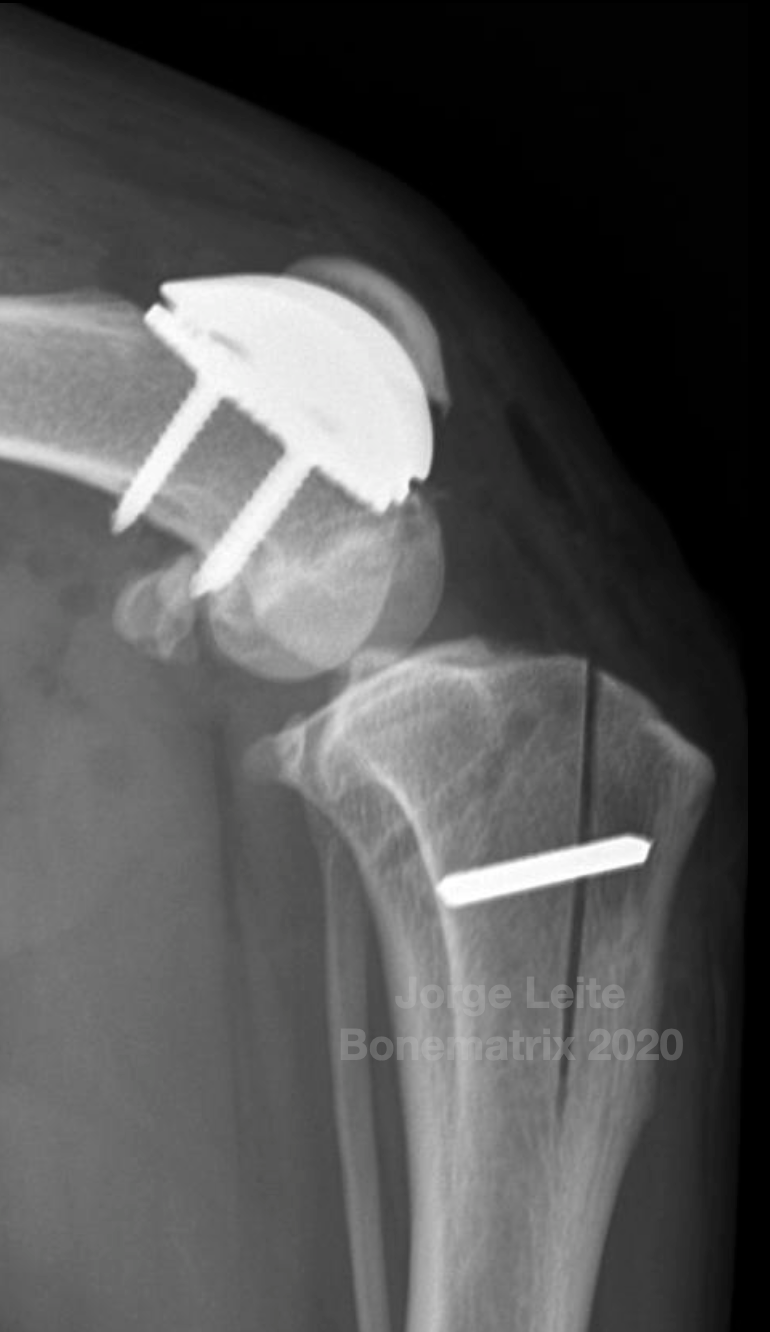

Plano cirúrgico: PGR + TTTT

• 22º de anteversão femoral

• 99º de aLDFA com severa erosão cartilagínea

• 10º de torção tibial externa estimada